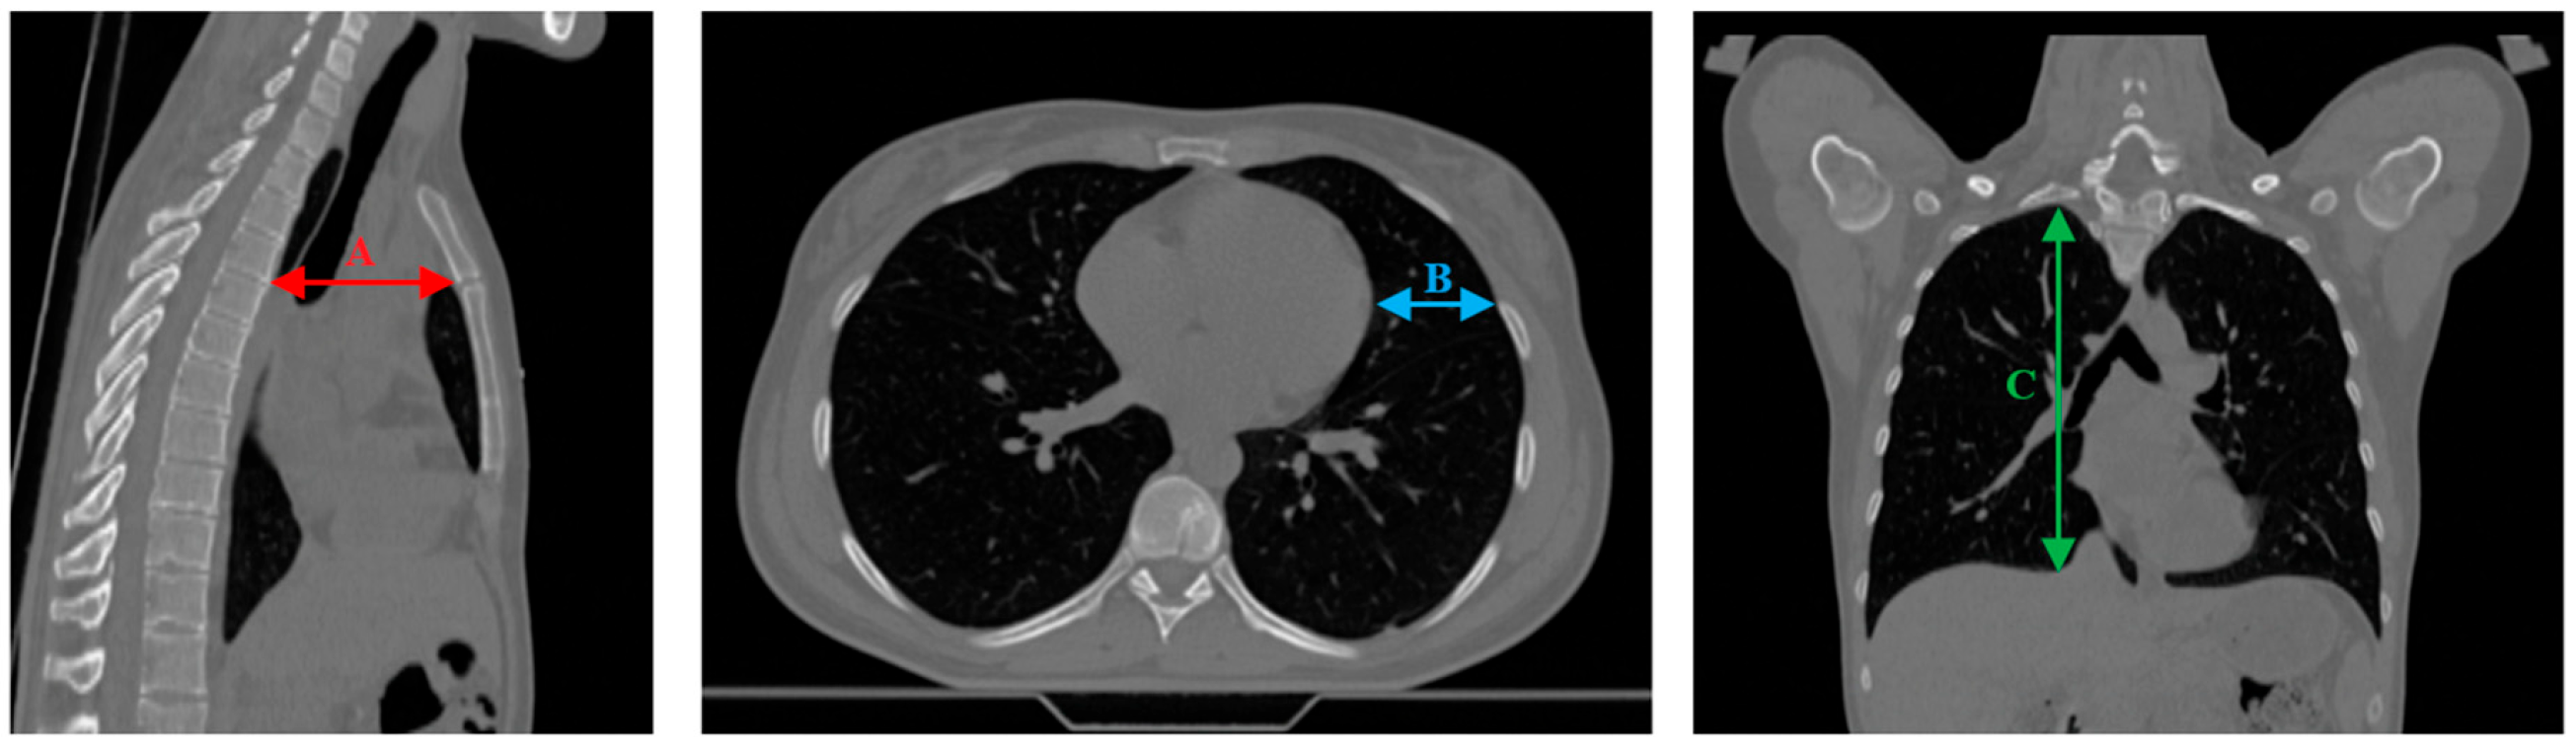

| Distance | #1 | #2 | #3 | #4 | #5 | #6 | ||||||

|---|---|---|---|---|---|---|---|---|---|---|---|---|

| Mean | Max | Mean | Max | Mean | Max | Mean | Max | Mean | Max | Mean | Max | |

| ∆A [cm] | 0.27 | 0.56 | 0.29 | 0.45 | 0.41 | 0.68 | 0.07 | 0.28 | 0.01 | 0.02 | 0.06 | 0.34 |

| ∆B [cm] | 0.70 | 0.90 | 0.37 | 0.77 | 0.45 | 1.54 | 0.88 | 1.58 | 0.23 | 0.57 | 0.32 | 1.51 |

| ∆C [cm] | 0.29 | 1.31 | 0.38 | 0.55 | 0.03 | 0.56 | 0.09 | 0.24 | 0.10 | 0.43 | 0.78 | 1.87 |